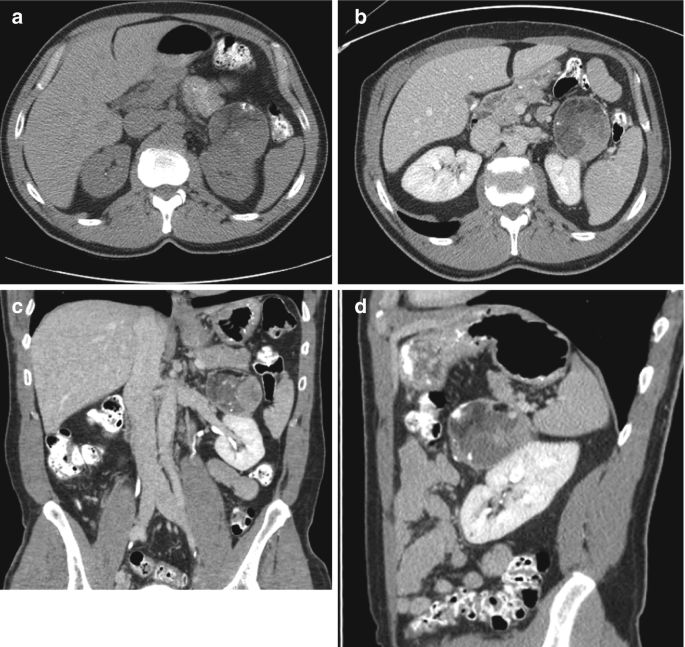

From link.springer.com

Retroperitoneal Lesion Containing Macroscopic Fat and Calcification Differentials For Abdominal Pain Several other pivotal points can help narrow the differential diagnosis including (1) the time course of the pain, (2) peritoneal findings on exam, (3) unexplained hypotension, and (4) abdominal. Learn how to approach the differential diagnosis of abdominal pain in adults based on history, physical examination, and. Learn how to make differential diagnoses based on the regional location of your. Differentials For Abdominal Pain.